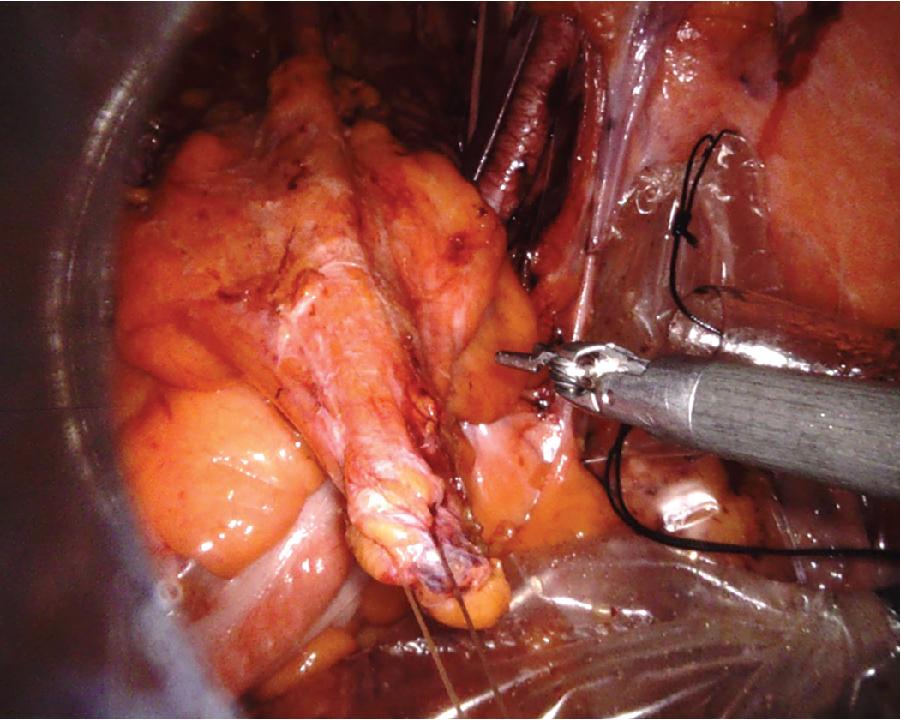

As the dissection proceeds and the target organ is mobilized, the position of the fourth arm needs to be regularly adjusted to maintain adequate (re)traction. Sometimes it can be useful to place additional traction sutures to improve exposure. A straight needle suture that is passed through the anterior abdominal wall can be used for retracting the peritoneum. Alternatively, traction sutures can be retracted through the assistant port ( Fig. 4.2 ) or with the use of the fourth arm.

Fig. 4.2, Tissue Traction With a Traction Stitch.